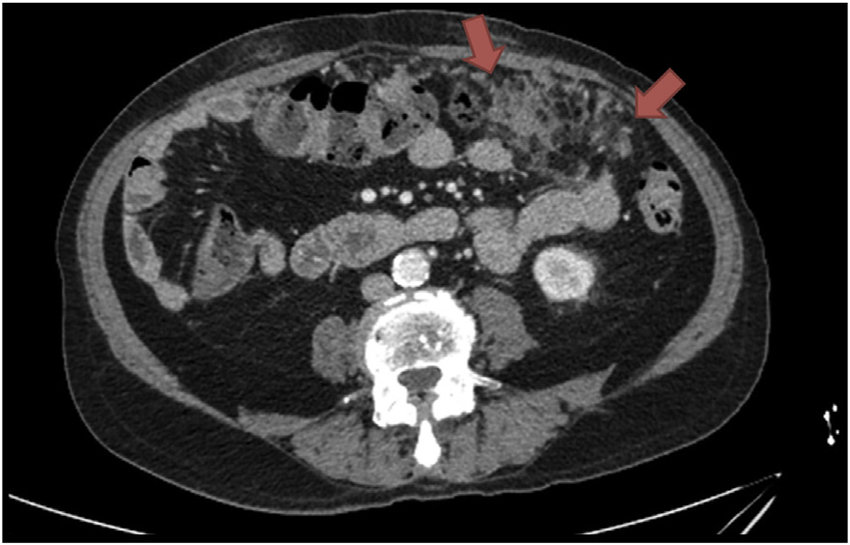

Omental Caking Radiology

The amount of fat in the omentum will vary with the size. The width of the omental cake is variable. The extent of the disease will be visible in the CT scan. The band of fatty tissue has a smudged appearance. Soft tissue nodules are enhanced when the disease progresses.

The normal fat is replaced when the omental rises abnormally. The cause of this condition is equally important to discover the severity of this condition. Ascites can be associated along with omental caking. The omentum, which is enormous, is seen as a big mass with lymphatics and milky spots. The clearance of pathogens is dependent on these milky spots.

A CT scan is the first diagnostic tool used for the diagnosis of Omental caking. If the images are not clear or any supporting evidence is needed, then MRI is used. Gastrointestinal contrast should be administered before MRI. Iodinated IV contrast material is used in imaging to get a clear picture of the thickness of the omentum.